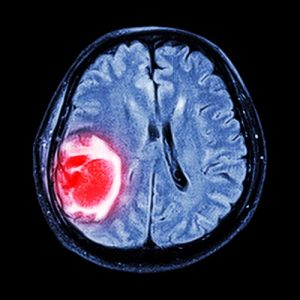

Методы лечения глиобластомы в Германии

Подход к лечению определяется индивидуально. Дело в том, что патологические клетки такого типа достаточно устойчивы к конвенциональным видам терапии, а здоровые клетки головного мозга — наоборот, могут легко повреждаться классическими химиопрепаратами. Дополнительную трудность составляет то, что большинство цитостатиков не могут проникнуть к опухолевым клеткам через гематоэнцефалический барьер. Поэтому врачи применяют комплексный подход.

Диагностика глиобластомы головного мозга в Германии

Обследование занимает несколько дней, чтобы установить точный вид новообразования, пациента направляют не несколько видов исследований.

- Магнитно-резонансная томография.